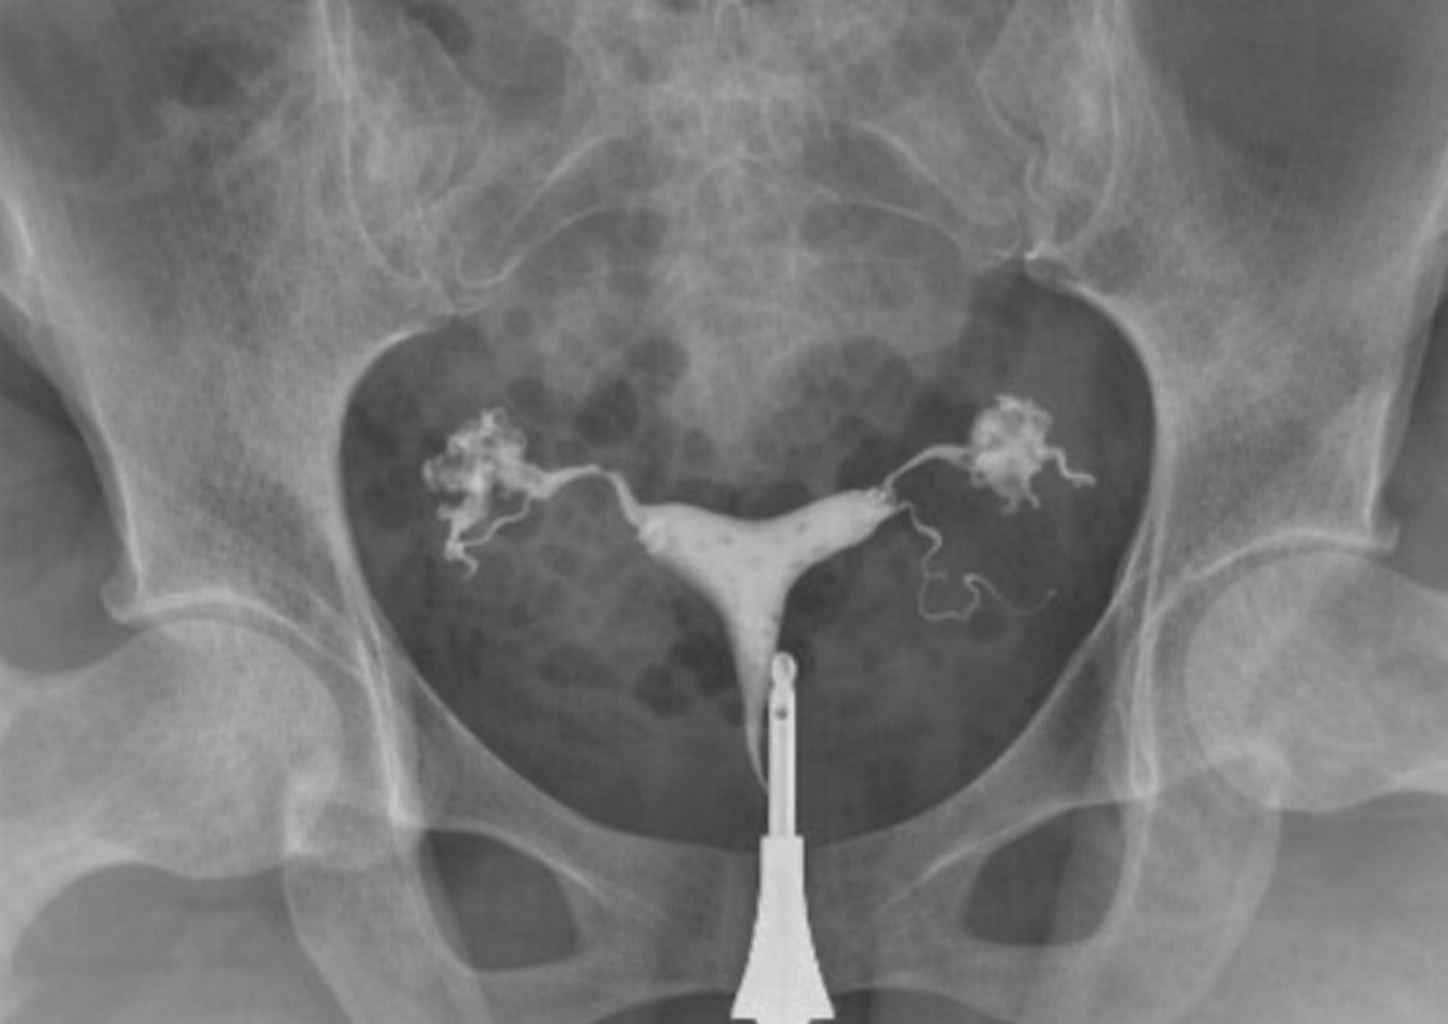

L’hydrosalpinx est une condition dans laquelle les trompes de Fallope se remplissent de liquide. Elle survient généralement à la suite d’infections antérieures, de maladies inflammatoires pelviennes ou de lésions des trompes. Cette situation peut perturber le fonctionnement normal des trompes et rendre la grossesse plus difficile.

En présence d’un hydrosalpinx, le liquide accumulé dans la trompe peut parfois refluer vers l’utérus. Ce liquide peut empêcher l’embryon de s’implanter dans la paroi utérine et peut réduire considérablement les taux de réussite, en particulier dans les traitements de fécondation in vitro. C’est pourquoi la planification du traitement est d’une grande importance chez les patientes diagnostiquées avec un hydrosalpinx.

Le traitement est généralement réalisé par chirurgie laparoscopique. Au cours de cette intervention, la trompe endommagée peut être complètement retirée (salpingectomie) ou la connexion entre la trompe et l’utérus peut être coupée afin d’empêcher le liquide d’atteindre l’utérus. La méthode à appliquer est déterminée en fonction de l’état de la patiente.